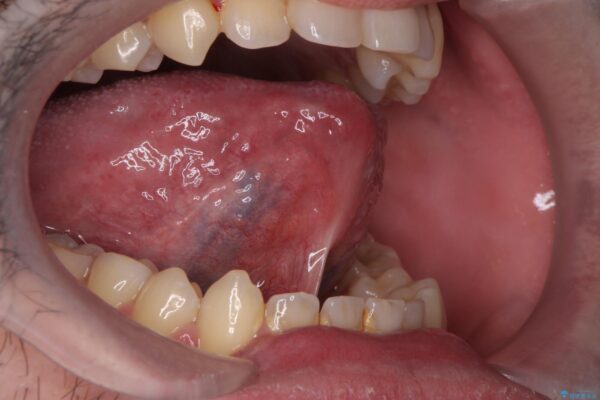

治療前

舌小帯を切除し滑舌を治したい 治療前画像 舌小帯を切除し滑舌を治したい 治療前画像